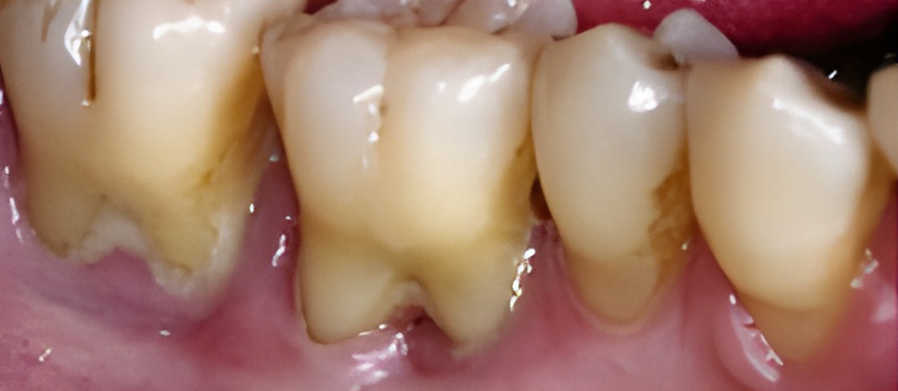

칫솔질과 치실질을 통해 매일 플라그를 제거하지 않으면 박테리아로 인해 잇몸 조직이 붉어지고 부어오르게 됩니다. 염증이 더 심해지면, 치아 주위 조직에 염증이 생기는 치주염으로 진행될 수 있습니다.

치은염을 치료하지 않고 방치하면 플라그가 뿌리로 퍼져 뼈와 연조직에 감염과 손상을 일으킬 수 있습니다. 잇몸이 치아에서 분리되어 물러나기 시작할 수 있으며 잇몸 라인 아래에 주머니가 생겨 플라크와 음식물이 쌓일 수 있습니다.

잇몸이 심하게 붓고 피가 자주 나며 치가가 흔들리기도 합니다. 치아 뿌리가 드러나기도 하며 때로는 잇몸에 고름이 나와 음식물을 잘 씹을 수가 없습니다.